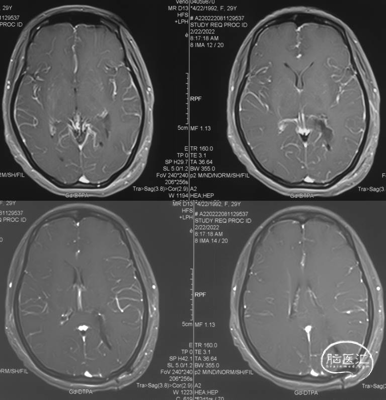

头颅MRI

左侧侧脑室三角区脑膜瘤。

左侧侧脑室三角区占位,边界清楚,不均匀强化,术前诊断良性脑膜瘤相对比较明确;患者年轻女性,无明确阳性体征,对手术微创及功能保留要求比较高;肿瘤相对较小,完全位于侧脑室内,且有明确的脉络丛供血;肿瘤位于三角区且为左侧优势半球,三角区皮层造瘘较大时可能术后会出现语言障碍及视野缺损明显。